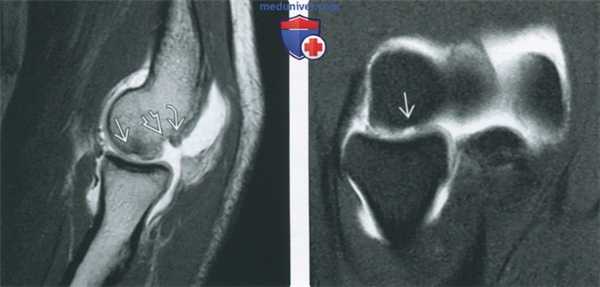

(Слева) МР-артрография в режиме Т1ВИ FS, сагиттальный срез: визуализируется костно-хрящевой дефект головки мыщелка плечевой коаи. В норме по задней поверхноаи головки мыщелка плечевой коаи имеется вырезка. В данном случае она более выражена за счет прилежащего остеофита.

(Справа) МР-артрография в режиме Т1 ВИ FS, этот же пациент: выявляется глубокий дефект хряща. В режиме подавления сигнала от жировой ткани сопутавующий отек костного мозга не определяется.